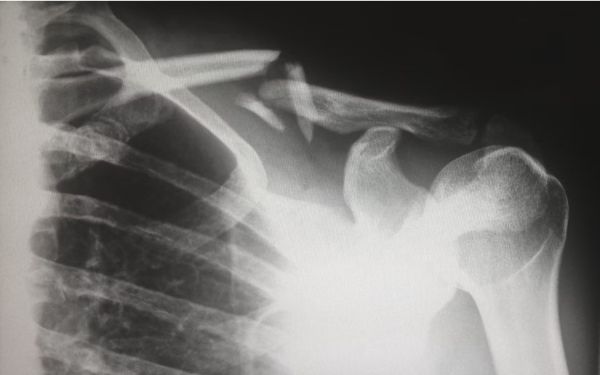

골절 위험 증가

골다공증의 가장 대표적인 초기증상은 골절 위험의 증가입니다. 뼈가 약해지면서 작은 충격이나 낙상으로도 쉽게 골절이 발생할 수 있습니다. 특히 손목, 고관절, 척추, 발목 등의 부위가 자주 골절되므로 주의가 필요합니다. 골절이 발생하면 통증, 부기, 혈종, 움직임 제한 등의 증상이 나타납니다. 골절이 의심되면 즉시 병원에 가서 X-선 검사를 받아야 합니다. 골절이 확진되면 골절 부위에 깁스나 부목을 씌우고, 필요한 경우 수술을 받아야 합니다. 골절이 치료되고 나서도 골다공증 치료를 위해 약물이나 운동 요법을 받아야 합니다.